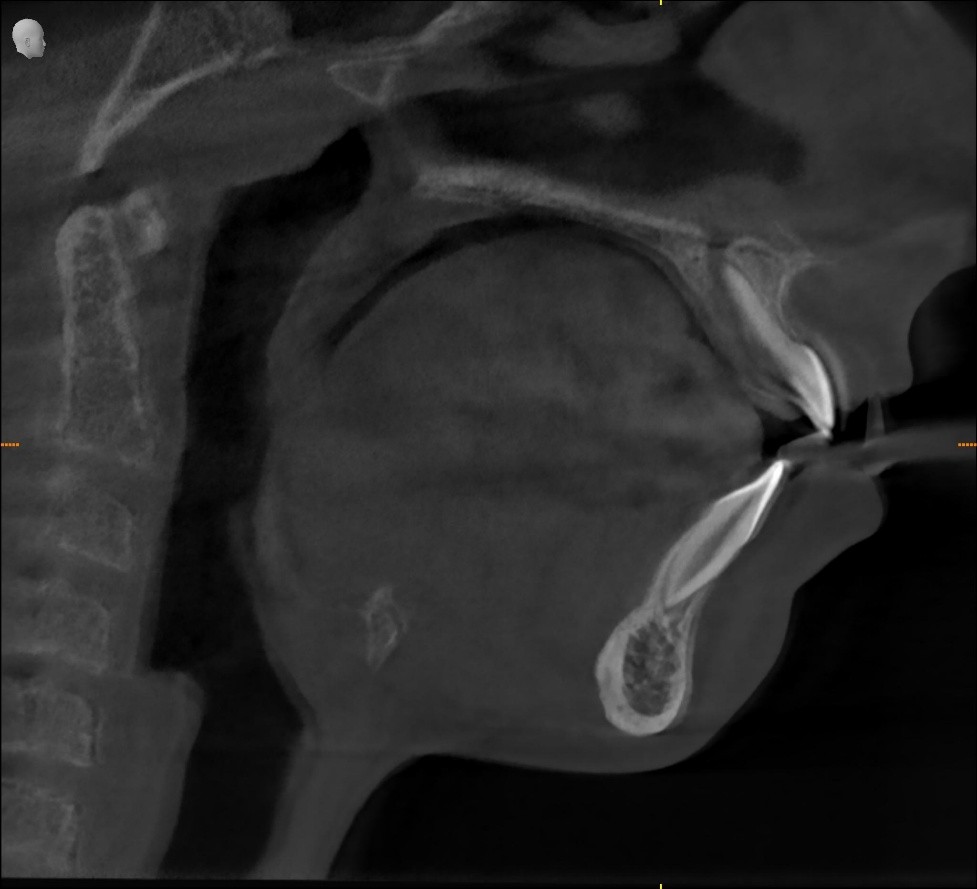

Sourya underwent a comprehensive airway-focused assessment, including:

- Targeted radiographic analysis — only when it altered management

Sourya was diagnosed with:

Pediatric airway dysfunction characterized by compromised nasal breathing, underdeveloped maxilla, altered tongue posture, and compensatory oral breathing

In simple terms:

His airway was restricting how his face, jaws, and body were growing.